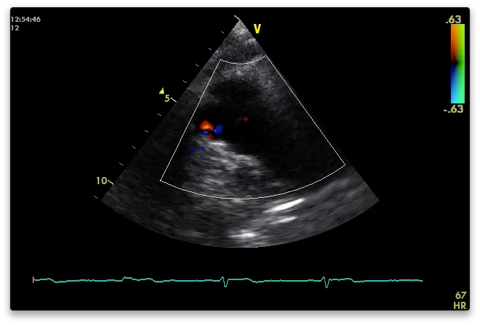

PRVO

From the PLAX view tilt the probe towards the patients left shoulder.

2D

Capture

RVOT, pulmonary valve and pulmonary artery visible.

Look for thrombus (PE)

Colour

PV - stenosis or regurg